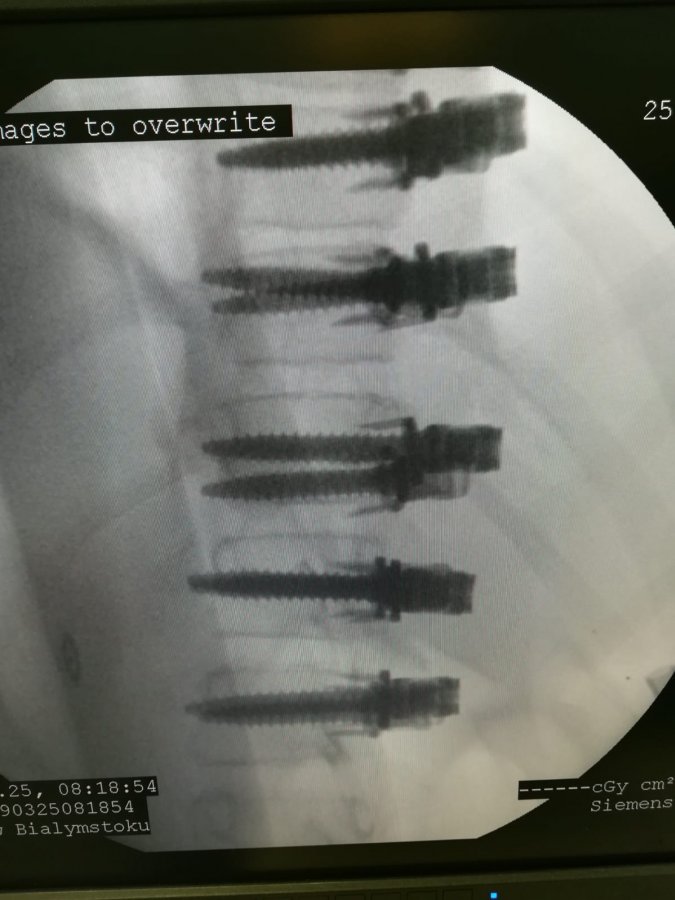

W końcu marca w Białymstoku wykonano operację korekcji skoliozy idiopatycznej techniką bez usztywniania kręgosłupa, tzw. VBT (ang. Vertebral Body Tethering). To autorskie opracowanie światowej sławy chirurgów kręgosłupa z USA dr Darryl Antonacci i prof. Randal Betz z Institute for Spine and Scoliosis. Metoda ta polega na wszczepieniu w kręgosłup ruchomych prętów elastycznych (wymiennie używa się też określenia śruby elastyczne i taśmy elastyczne), bez usztywniania kręgosłupa. - Pręty umożliwiają dziecku powrót do normalnej aktywności w ciągu sześciu tygodni, nawet z gimnastyką artystyczną i tańcem włącznie - opisywała zabieg prof. Anna Wasilewska, dyrektor szpitala dziecięcego.

Operacji poddano 11-letnią dziewczynkę z Białegostoku. Wykonali ją dr Darryl Antonacci w asyście ortopedów z Kliniki Ortopedii i Traumatologii Dziecięcej UMB dra Pawła Grabali i szefa kliniki dra Tomasza Guszczyna. Tego typu zabiegi, prócz USA, wykonują ledwie cztery ośrodki w Europie, zaś dr Grabala jest jednym z kilku osób na świecie, która odbyła staż u prof. Antonacci’ego.

- Istotne w tej operacji jest też to, że są one mało inwazyjne. Wszczepienie systemu śrub i taśm elastycznych do kręgosłupa następuje z dostępu przedniego. Zaletą jest prawie niewidoczna blizna, oraz szybki powrót do pełnej sprawności i aktywności fizycznej - dodaje dr Tomasz Guszczyn.